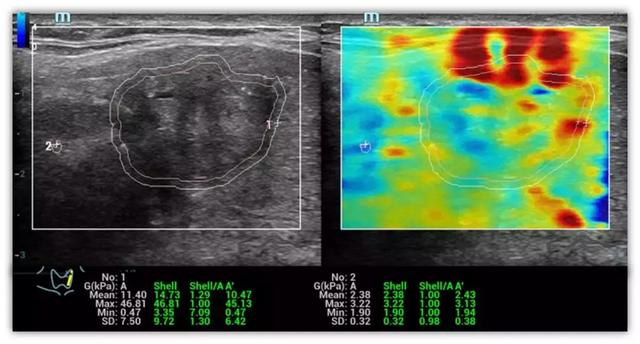

迈瑞独有的可量化剪切波弹性比和剪切模量

大会期间,深圳人民医院超声科董发进博士分享了基于迈瑞Resona 7的多模态弹性成像技术关于甲状腺癌诊断的最新研究报告。迈瑞的剪切波弹性成像提供了应变弹性和剪切波弹性成像的多模态弹性技术进行组织硬度的测量,其弹性比(Elastic Ratio, EI)和剪切模量(shear module, G)可以用于进行定量分析。研究报告的目的是应用全新可量化的剪切波弹性比和剪切模量进行甲状腺恶性结节的评估。

研究结果显示,恶性甲状腺结节的平均弹性比明显低于良性结节。(P<0.001)敏感度和特异性分别达到71%和73%。恶性甲状腺结节的剪切模量最大值,平均值和标准差明显高于良性结节。(P<0.005)。在剪切模量最大值的参考值(cut-off value)设置在15.82kPa的条件,能获得最高的AUROC值(0.84),敏感度和特异性分别达到79.17%和79.03%。研究结果表明,可量化的剪切波弹性技术将会是一个新的辅助诊断甲状腺结节良恶性的超声工具之一。

甲状腺结节